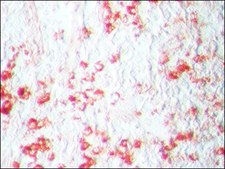

AEC Staining Kit has been used as a substrate

- for developing the extravidin peroxidase antibody in cell-seeded matrice sections using histology and immunohistochemistry methods

- for streptavidin-horseradish peroxidase in peripheral blood mononuclear cells in ex vivo enzyme-linked immunospot (ELISPOT) assay

- for mouse IgG biotinylated secondary antibody in immunohistostaining of epididymal fat pads

Kit contains 3 mL of concentrated acetate buffer, 3-amino-9-ethylcarbazole (AEC) chromogen and hydrogen peroxide in a dropper bottle for easy dispensing. Directions for use with each application are included.

Use this protocol to for the entire immunohistochemistry (IHC) procedure through staining and visualization of specific antigens in paraffin-embedded tissue sections.